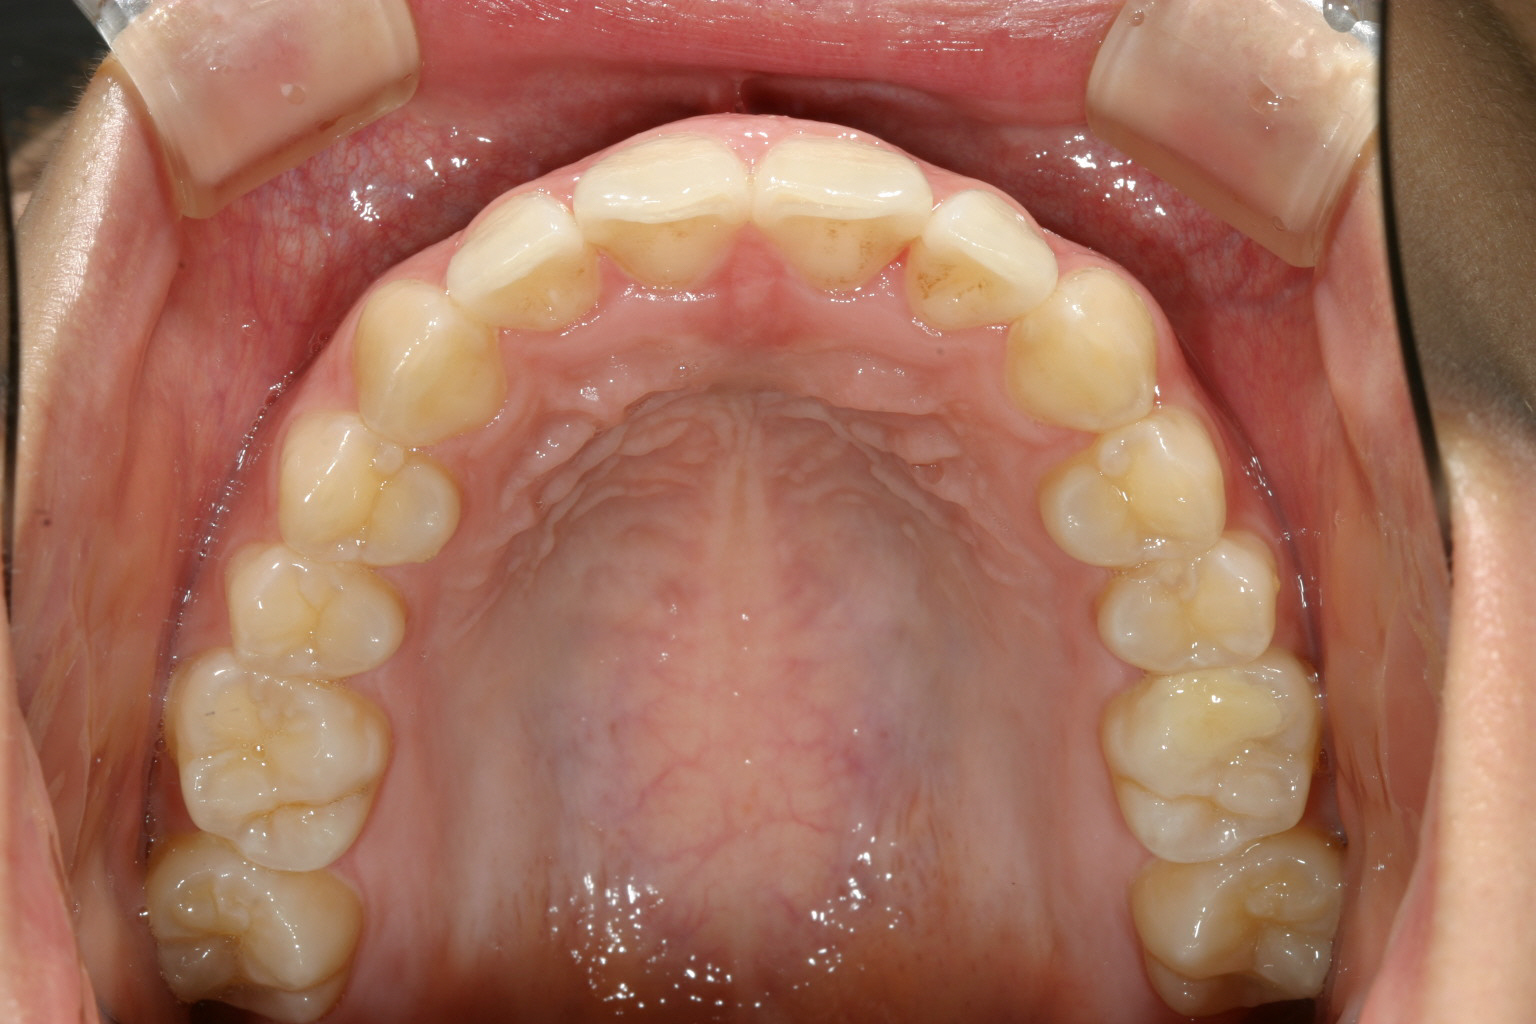

前歯が翼状捻転してます。

綺麗に改善しました。

こちらも綺麗なアーチになりました。

こちらの症例は僅かな翼状捻転だけが問題でしたからインビザラインで難なく改善しました。